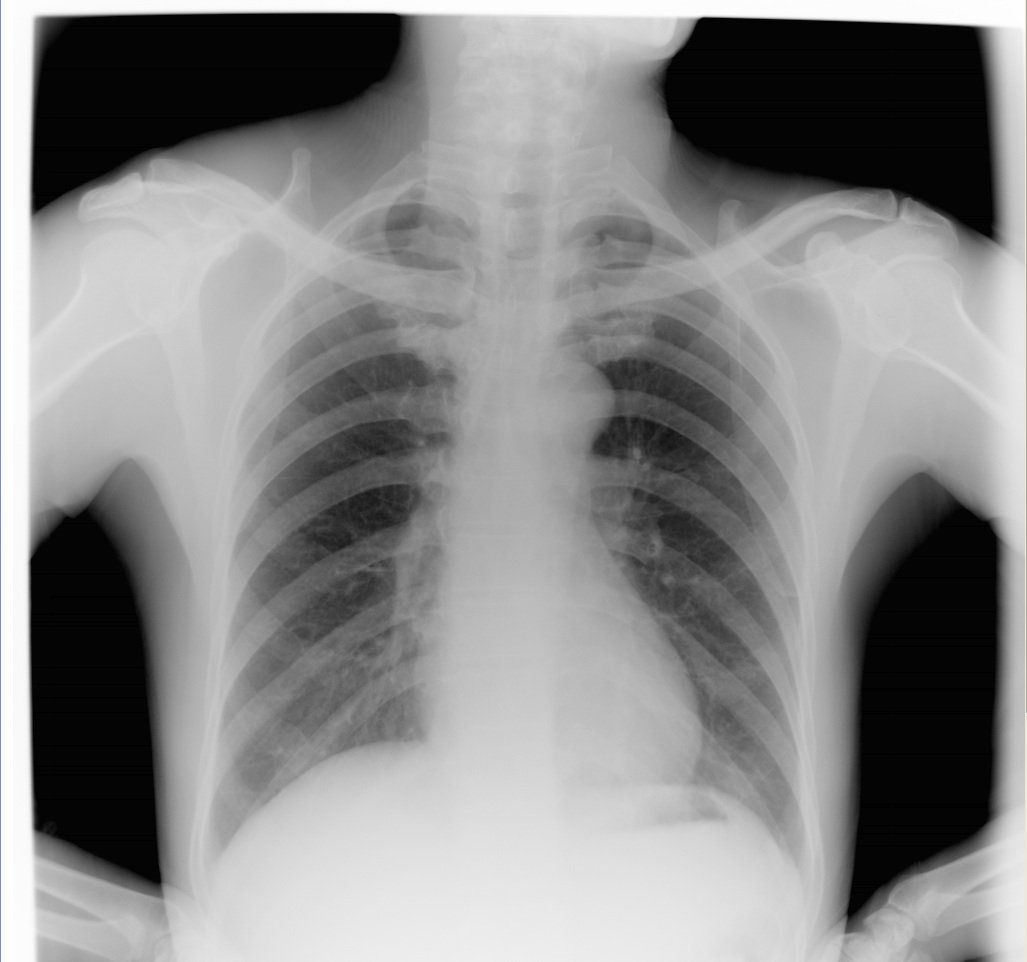

增强效果